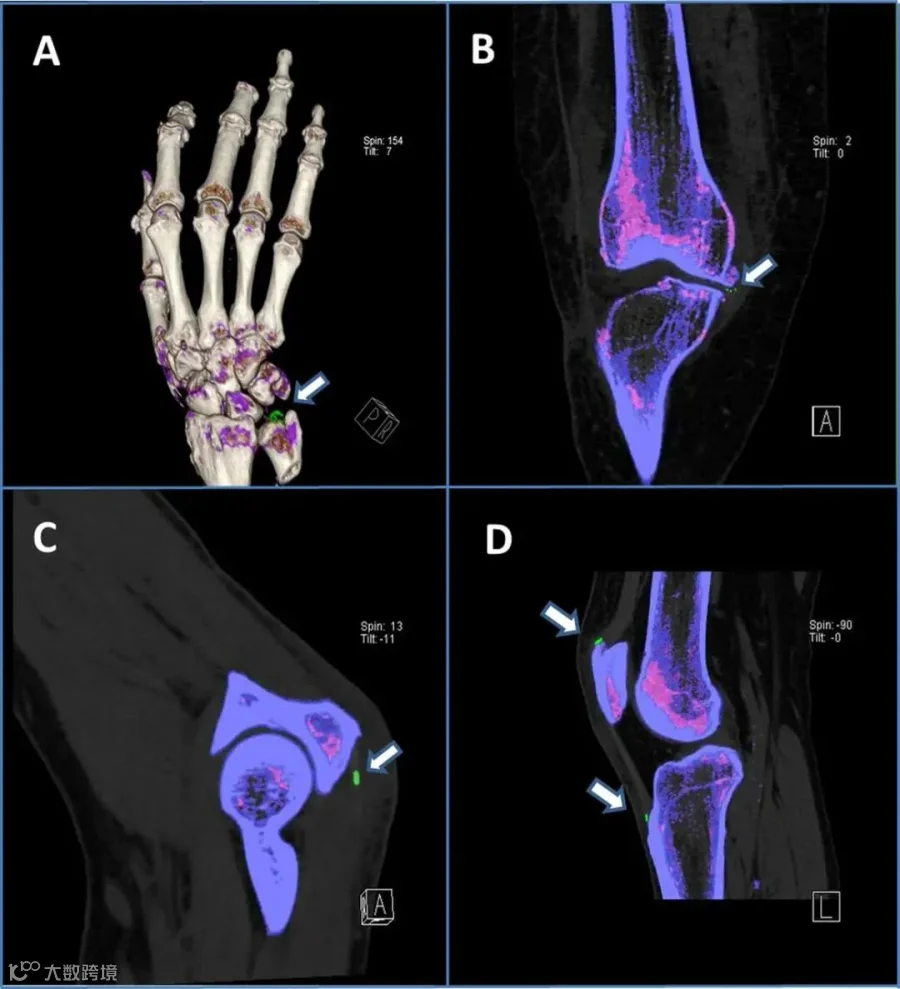

其中双源能谱CT项目是尤为重要的一项,它是明确关节部位是否存在“痛风结晶”的快速、无创、直观且最有效诊断痛风的方法。

它可以准确检测出尿酸盐晶体位置,同时可测量尿酸盐的体积,可以作为痛风的筛查和诊断工具。

▽你能找到绿色的痛风石吗?